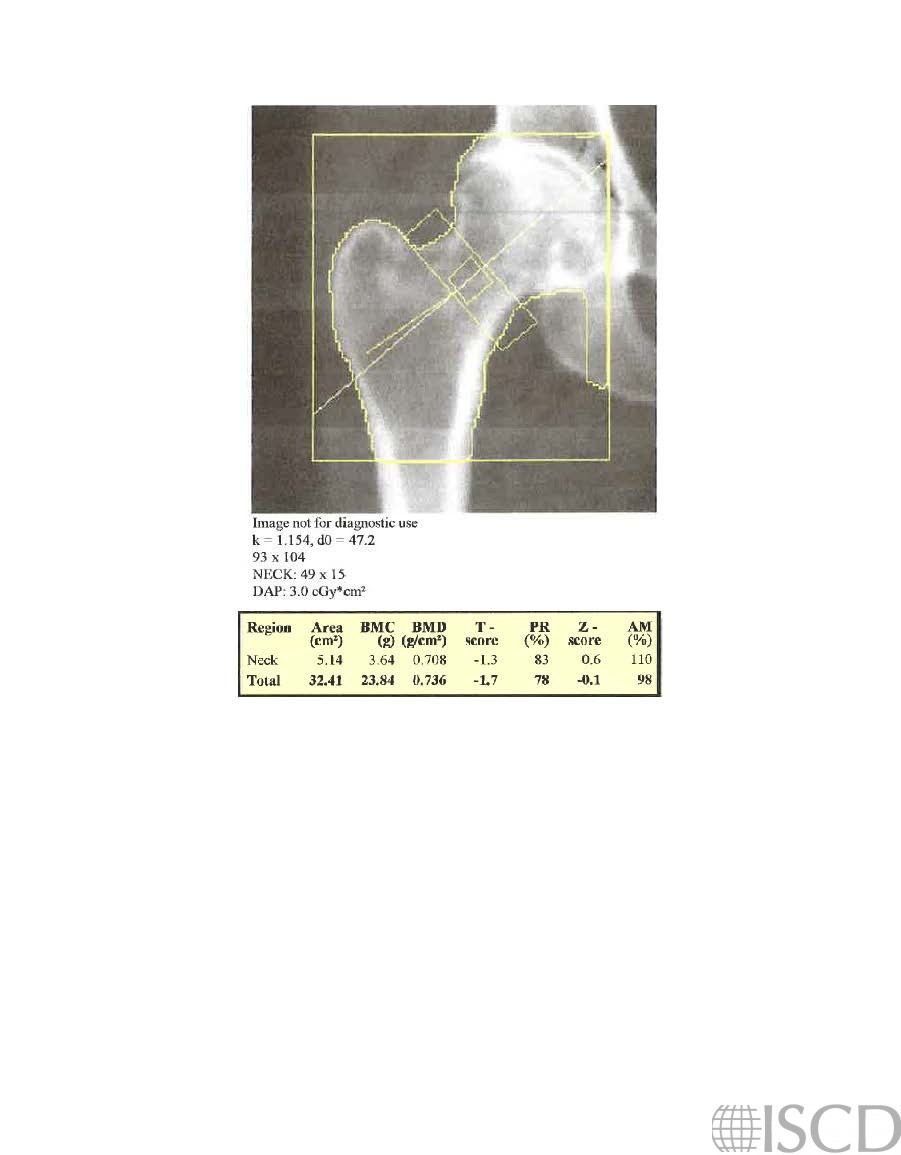

Incorrect Hologic Femoral Neck Box Width

The right Hologic femoral neck box width is incorret in this analysis. The default width is 15 pixels.